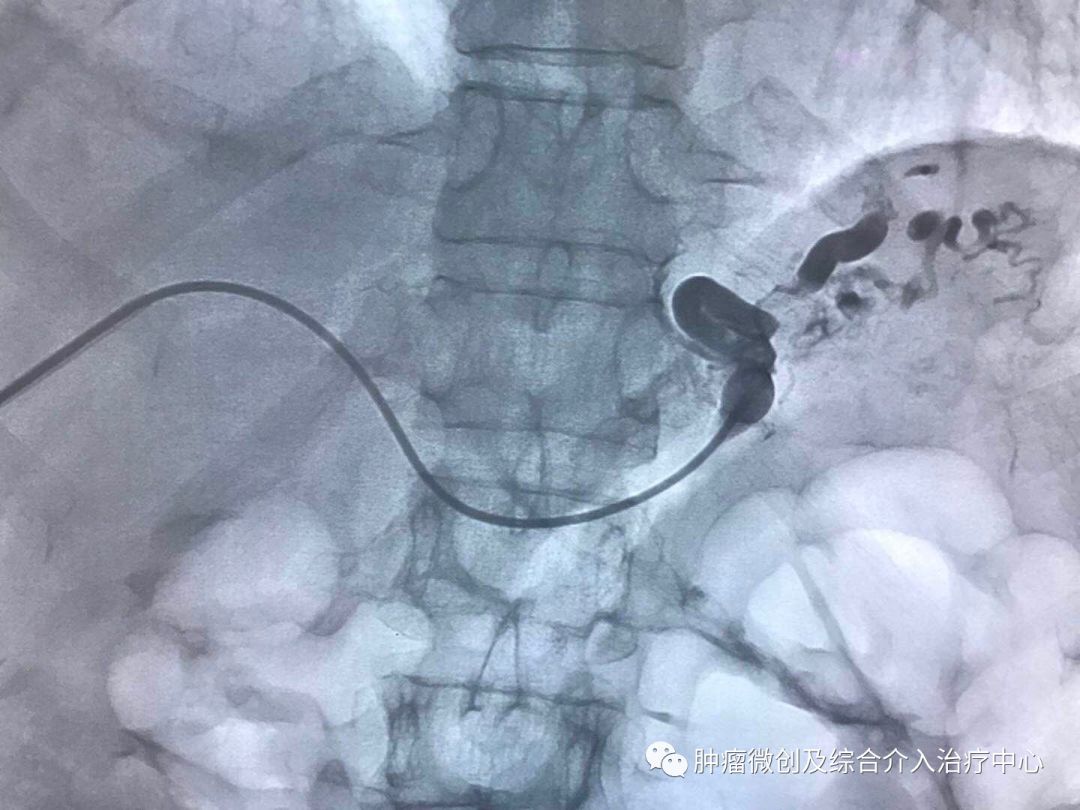

(介入栓塞术后提示无肾动脉出血肾动脉-栓塞成功)